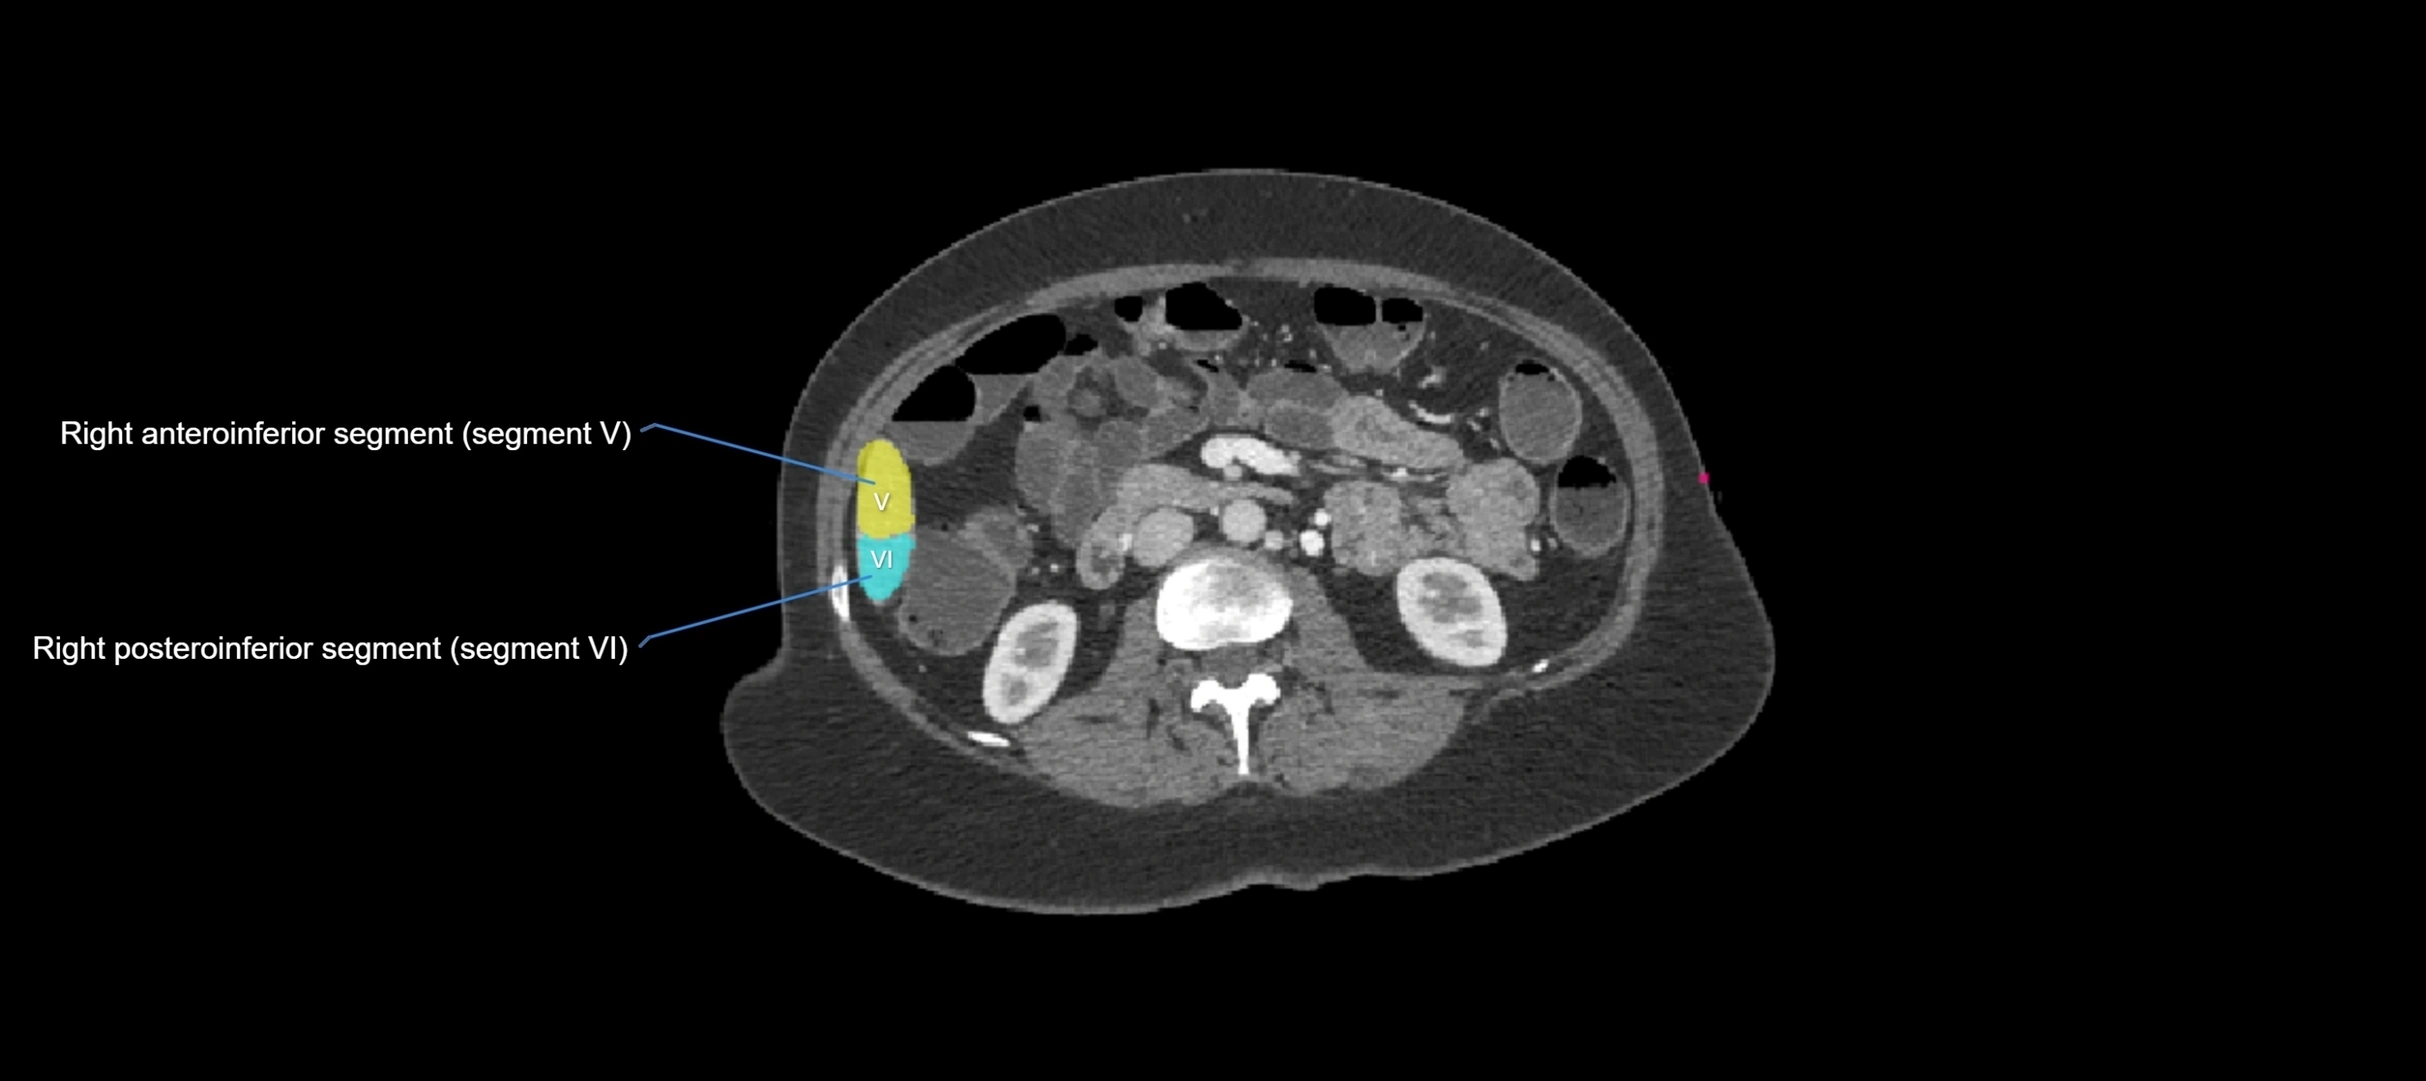

CT Image

image